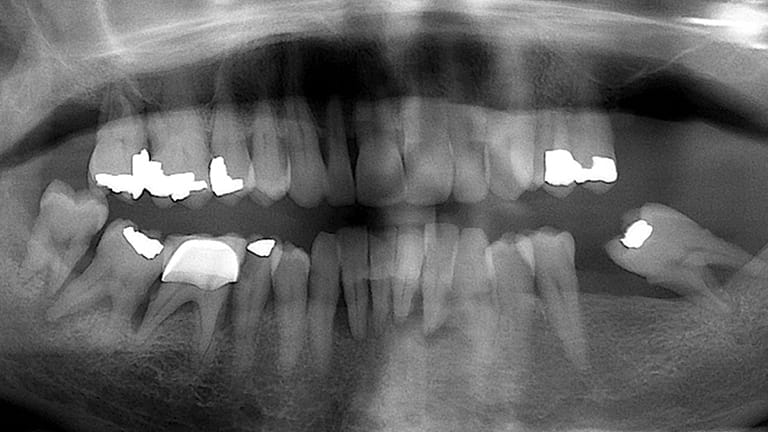

Dental implants are a titanium "root" which can be placed into the jawbone. Once integrated with your bone, the implant can be used to support a crown, a bridge, or secure a complete denture. Dental implants may be used to eliminate partial plates and dentures. The success rates for dental implants are extremely high which is due in part to the fact that root-form implants are made of a biocompatible material, titanium.

Below is a few examples of what DENTAL IMPLANTS can do for you and your smile!